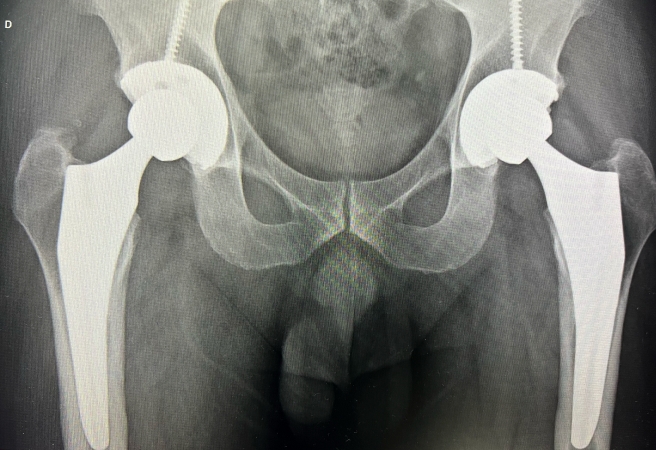

Sobre a cirurgia de prótese de quadril, o ortopedista explica que está cada vez mais moderna. “Hoje contamos com próteses de materiais muito resistentes, técnicas menos invasivas, recuperação mais rápida e até cirurgia com auxílio de robôs. Isso significa mais precisão, menor risco de complicações e uma prótese que dura mais. Muitas vezes, o paciente já caminha no dia seguinte à cirurgia”.